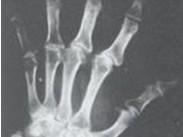

卡斯欽-貝克病(Kaschin-Beck disease)即大骨節病,是一種地方性軟骨骨關節畸形病,是以軟骨壞死為主的變形性骨關節病。多發生于兒童和少年,主要侵犯兒童和青少年的骨骼與關節系統,導致軟骨內成骨障礙、管狀骨變短和繼發的變形性關節病。致管狀長骨發育障礙,關節增粗、疼痛、肌肉松弛、萎縮和運動障礙。患者以身材矮小、短指、關節畸形、步態異常(呈典型跛行、鴨步)等為特征。本病尚有“矮人病”、“算盤子病”、“柳拐子病”等之稱。

- 常見癥狀:軟骨發育不良與骨骼畸形、肌肉萎縮、指(趾)和小腿出現痙攣及隱痛、步態異常、體型異常、關節疼痛